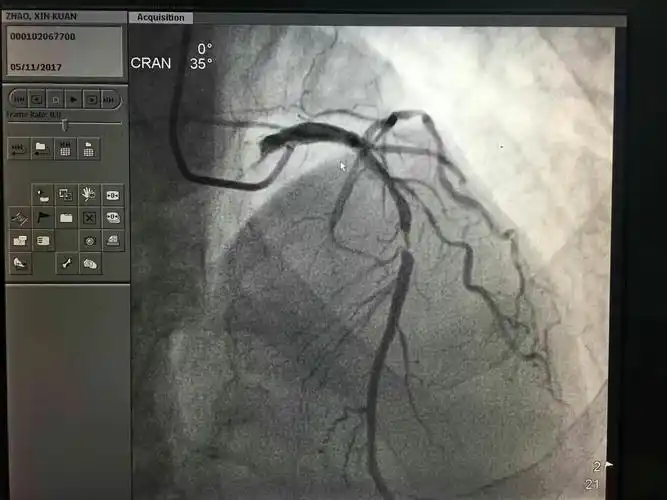

冠状动脉造影

血管造影一般指冠状动脉造影,是诊断冠状动脉粥样硬化性心脏病的一种

选择性冠状动脉造影就是利用血管造影机,通过特制定型的心导管经皮

冠脉病变,造影确诊